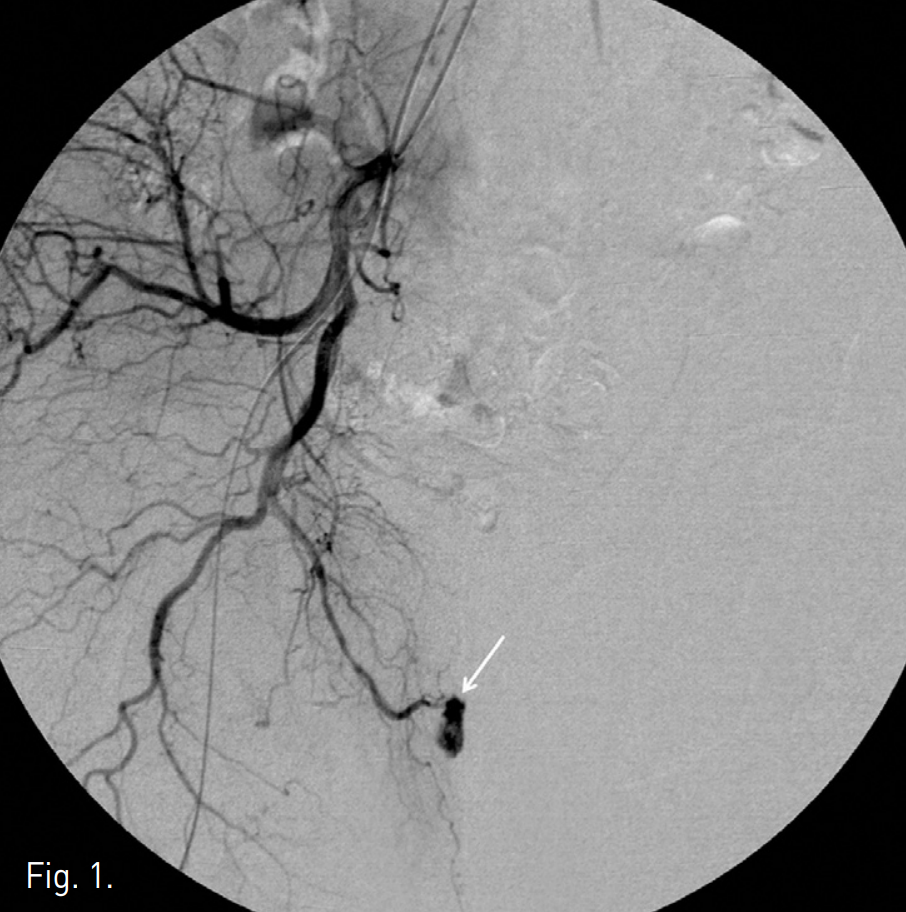

Fig. 3

Left internal iliac angiogram shows patent dorsal penile artery (arrow) without evidence of arterio-cavernous fistula.